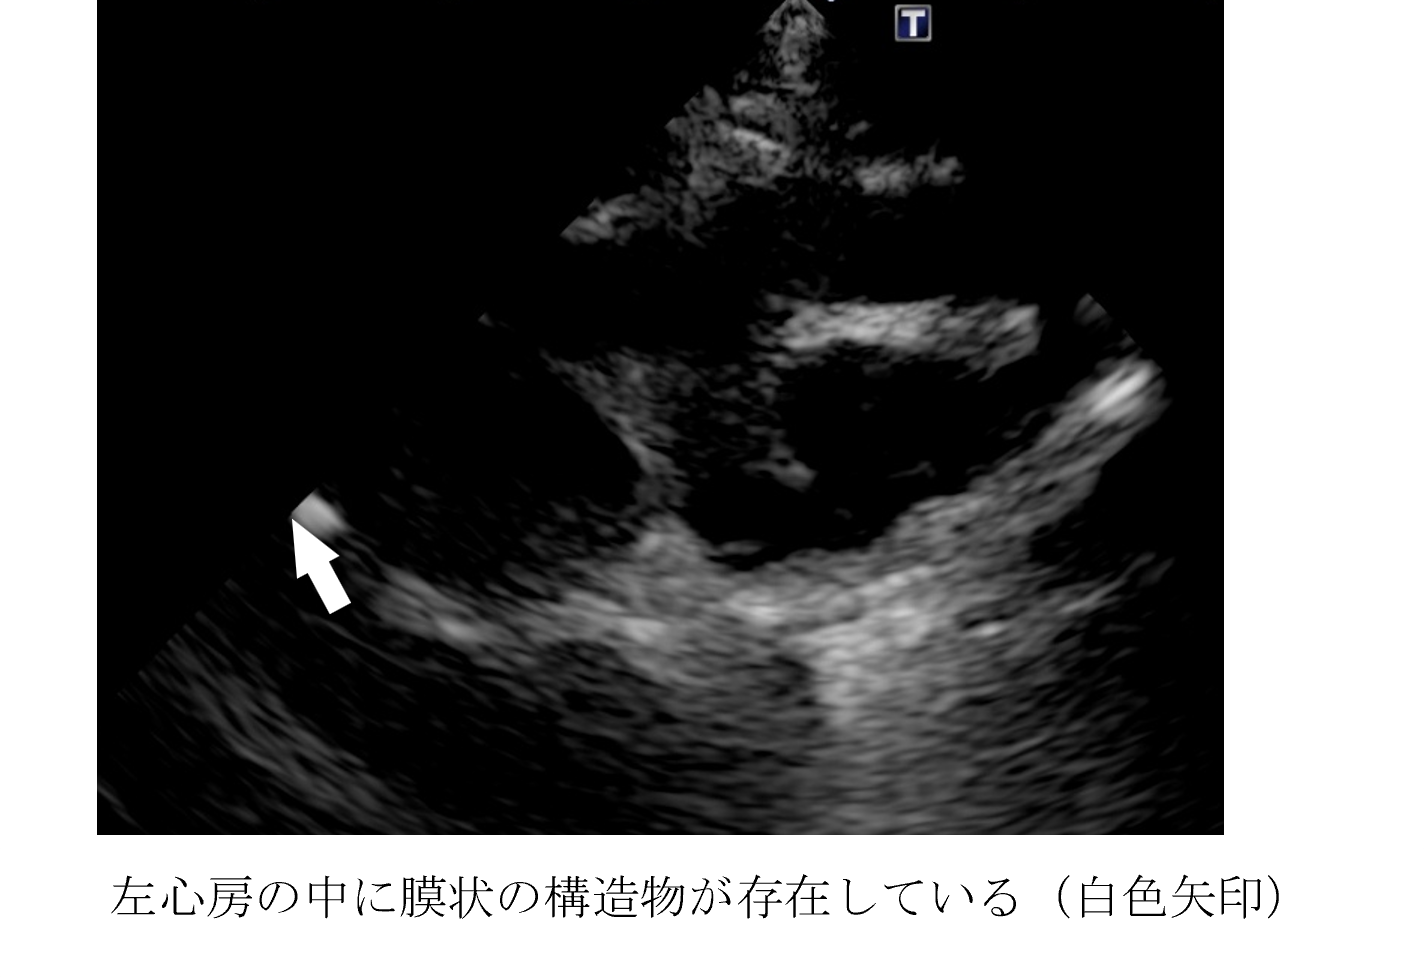

各種検査より、三心房心と診断しました。

三心房心とは、右心房または左心房の内部に隔壁があり、心房が3つに分かれている状態を指します。このため、心房が3つある状態になり、3つの心房がある心臓ということで三心房心と言います。

先天性心疾患の一種で、比較的稀な心奇形とされています。